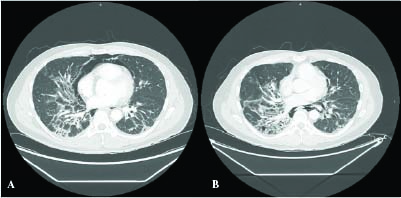

Figure 1

Figure 1. Chest X-rays on the initial visit show subcutaneous emphysema over the lower neck and upper chest with multifocal bilateral pulmonary infiltrates.